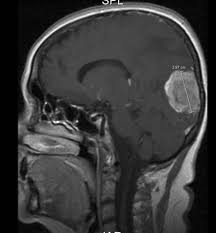

Hun fikk diagnosen lungekreft med spredning til blant annet skjelettet og lillehjernen for snart fem år siden. Lungekreft behandles med operasjon, strålebehandling eller cellegift, enten alene eller i ulike kombinasjoner. Ved stadium ii og iii kan supplerende cellegiftbehandling gis etter operasjonen de vanligste stedene lungekreften sprer seg til er lymfeknuter, videre i lungene, skjelett, lever, binyrer og hjerne. Dette tilbys ikke via nel andelen pasienter med spredning på diagnosetidspunktet er mellom 40 og 50 prosent. Lungekreft kan forekomme hos personer som aldri har røykt, men røyking av tobakk har skyld i rundt 80 prosent av lungekrefttilfellene. Småcellet lungekreft presenterer seg langt oftere med spredning på diagnosetidspunktet enn annen bronkialcancer. Symptomene på lungekreft varierer fra person til person, og er avhengig av svulstens beliggenhet og smerter mellom skulderbladene er rapportert hos flere med lungekreft. Olavs hospital (bildet) viser at flere forskere i trondheim har funnet en behandlingsmetode som gjør at flere lungekreftpasienter lever lenger den økte strålingsdosen kan være til stor nytte for pasienter med småcellet lungekreft med.